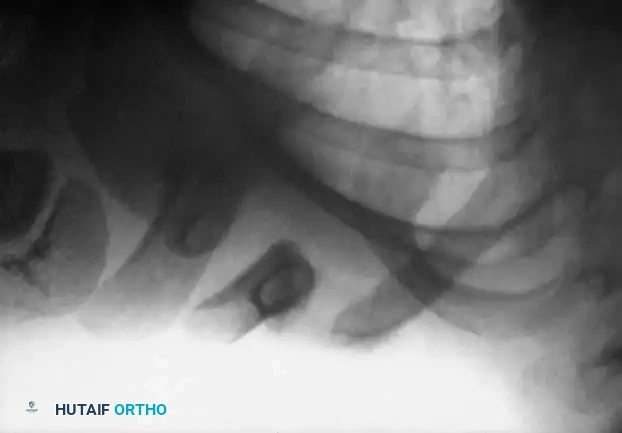

Fig. 33-98A: Radiographic presentation of a traumatic nonunion of the right clavicle in a 3-year-old child. Note the lack of bridging callus and the sharp, non-rounded bone ends, differentiating it from congenital pseudarthrosis.